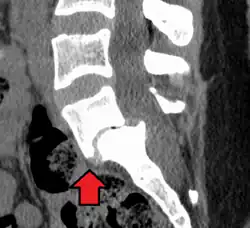

Спондилолистез L5-S1

Боковая рентгенограмма покажет степень смещения позвонка к нижележащему:

• Степень I — смещение до 25 %.

• Степень II — смещение от 26 % до 50 %.

• Степень III — смещение от 51 % до 75 %.

• Степень IV — смещение от 76 % до 100 %.

• Степень V развивается, когда позвонок полностью отделяется от соседнего позвонка (спондилоптоз).